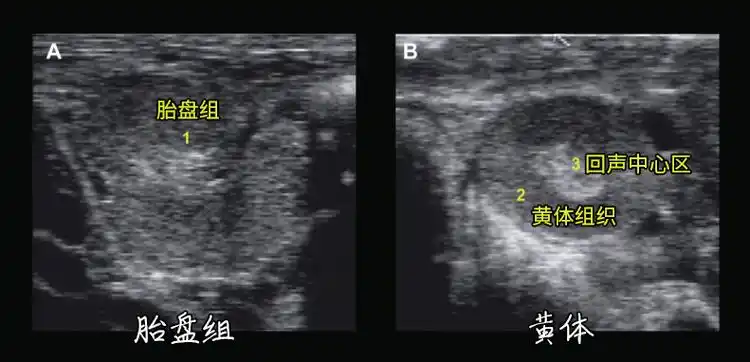

牛卵巢异常的兽用b超图像_黄体_卵泡_超声